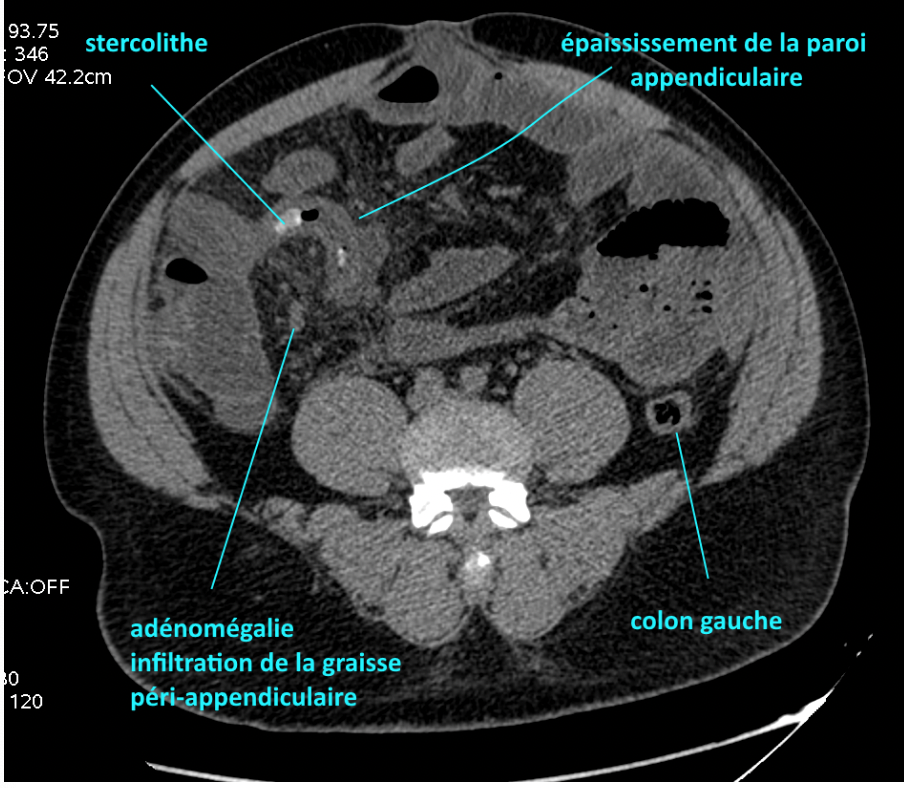

Aspect TDM appendicite dite typique

A

• Augmentation taille appendice et paroi

• Infiltration graisse du méso appendice

• Présence éventuelle stercolithe

• Présence éventuelle complication